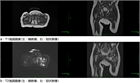

1. 乳児可能性股関節炎を疑う場合には、早急な診断確定が必要である(推奨度1)

1. 診断確定には血液検査と共にMRIが推奨される(推奨度1)

1. 診断確定後は速やかに外科的処置と抗菌薬の全身投与を開始する(推奨度1)